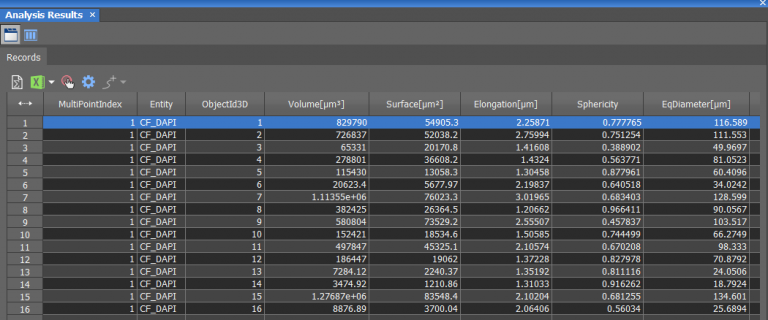

Morphological studies of the acinar structures were accomplished using NIS-Elements General Analysis (GA3), an analysis pipeline with artificial intelligence (AI) capabilities. The combination of multiple conventional segmentation tools and AI techniques can enable customized measurements tailored to specific experiments, and this can be employed across high-content datasets as well. As represented in Figure 7A, we created an analysis pipeline based on five steps: Denoising, Deconvolution, Thresholding, Object counting and Measurements. The previously acquired high-content data can be automatically analyzed using this procedure, obtaining information about volume (um3), surface (um2), elongation (um), sphericity and diameter (um), allowing us to gain more insight into the morphological characteristics of 3D breast cultures (Figure 7B).

A

B

Figure 7: Automated high-content data analysis for morphological profiling of 3D breast culture acini. Analysis pipeline built via GA3 analysis (A) to obtain information on the volume, surface area, elongation, sphericity, and diameter of 3D breast spheroids (B).

Using such an automated analysis pipeline, we have collected a wide range of information useful in understanding how mutated Ras receptors affect the proliferation and morphology of acini. As shown in Figure 8A, acinar structures from cultures of non-malignant breast cancer typically have round symmetrical shapes. On the other hand, the acini from malignant breast cancer cultures cause a deformation in the 3D architecture which causes the shape of the acini to be more elongated and deconstructed. Notably, the spheroids derived from the MCF10A K-Ras engineered line has a significant volume increase compared to the control line (Figure 8B). In fact, the transforming contribution of the k-Ras oncogene correlates with the increase in the cellular proliferative rate, and this causes an increase in volume already after 6 days in culture.

This powerful imaging system, coupled with software capable of automating acquisitions and analyses, made it possible to compare morphological characteristics between non-malignant (CTR) and malignant (K-Ras) cancer cells. Studying some morphological features such as volume, elongation, sphericity, diameter and surface, we found that malignant cancer spheroids display a loss of cell polarity during proliferation that alters acinar structure and architecture. 3D cellular models, therefore, are useful tools for re-creating in vitro tumor pathological phenomena. The combination of high-content microscopy with 3D cell models could thus contribute significantly to cancer research, especially in the validation of oncologically relevant molecules.